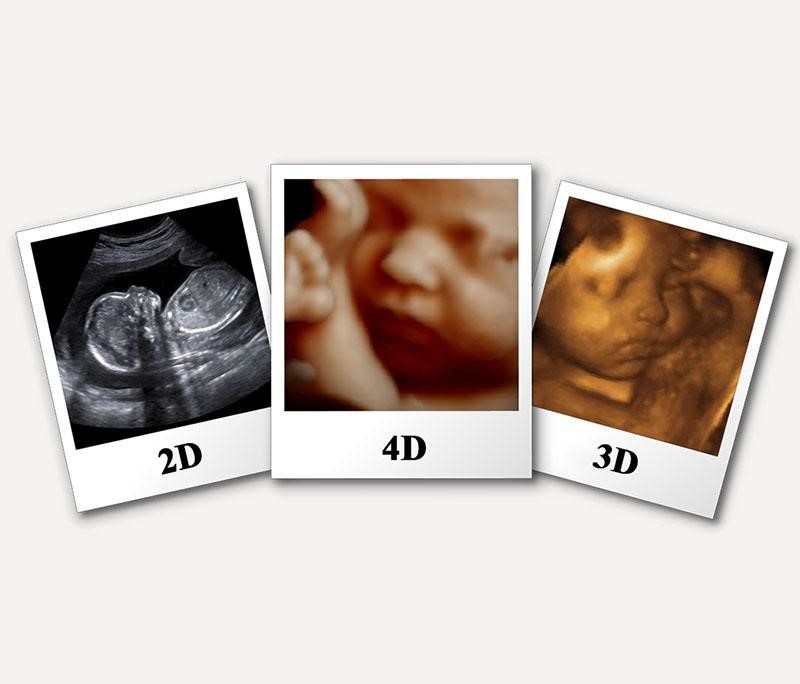

Siêu âm 3D giống với siêu âm 2D ở chỗ đều là siêu âm ba chiều. Nhưng siêu âm 3D cho kết quả là hình ảnh màuc, có kích thước lớn hơn, rõ hơn, tái hiện hình ảnh chân thực hơn siêu âm 2D rất nhiều.

Siêu âm 3D giúp mẹ bầu thấy rõ hình hài của thai nhi, khuôn mặt của bé cũng như sự phát triển qua từng ngày của bào thai. Cũng nhờ những chỉ số siêu âm cung cấp mà mẹ sẽ an tâm hơn trong quá trình dưỡng thai vì có thể kịp thời xử lý khi có dấu hiệu bất thường xảy ra.

Ngoài ra, cũng qua các chỉ số thu được mà siêu âm 3D có thể phát hiện những dị tật bẩm sinh như những vấn đề về tim mạch, thần kinh, hở môi, hở hàm ếch,… Qua đó sẽ giúp bố mẹ có những kế hoạch phù hợp để chăm sóc sức khỏe, chuẩn bị sẵn sàng để con chào đời.

• Ccung cấp hình ảnh ở nhiều góc độ khác nhau nên hình ảnh sắc nét và dễ nhìn.

• Giúp bác sĩ có thể quan sát các mô mềm trên bề mặt da ngoài em bé để phát hiện dị tật bẩm sinh